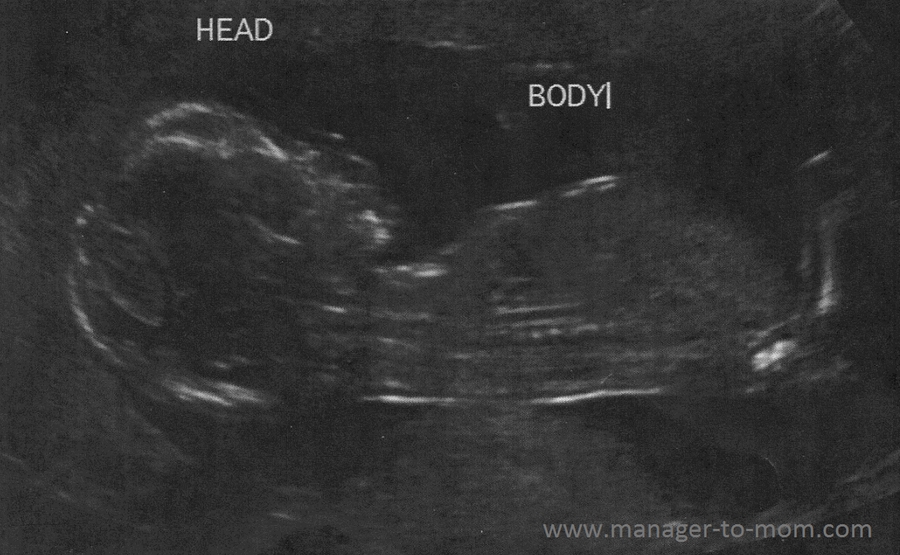

If the scan finds there might be a problem, what happens next? Coincidentally, most also happen by 7 weeks' gestation. No analgesia is required for this ultrasound. What types of ultrasound are there? early ultrasound dating wrong

Ultrasound scans in pregnancy - Your choice will be respected if you decide not to have the scans, and your antenatal care will continue as normal. I was 10 weeks pregnant. early ultrasound dating wrong